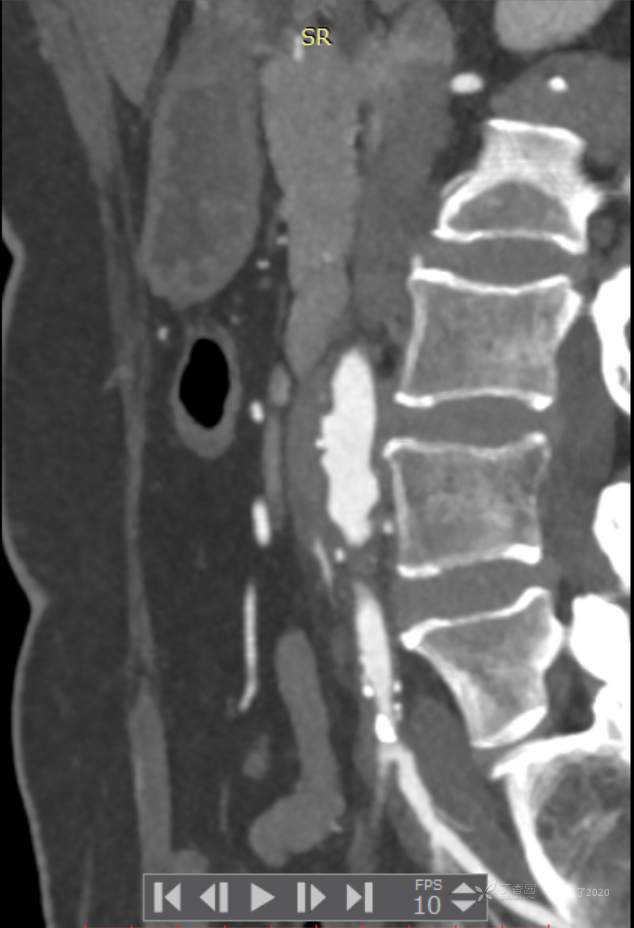

求助 | 女,61岁,下腹部、腰及双髋关节隐痛1月余

II型糖尿病10年余,既往饮食控制血糖在7~8左右,今年1月份开始服用二甲双胍;2009年4月因“子宫肌瘤、双侧输卵管慢性炎症”行子宫及附件切除术;2021年1月体检发现双侧甲状腺多发结节,较大者12*7mm;高血脂10余年,近1月开始规律服药,控制不理想;无高血压